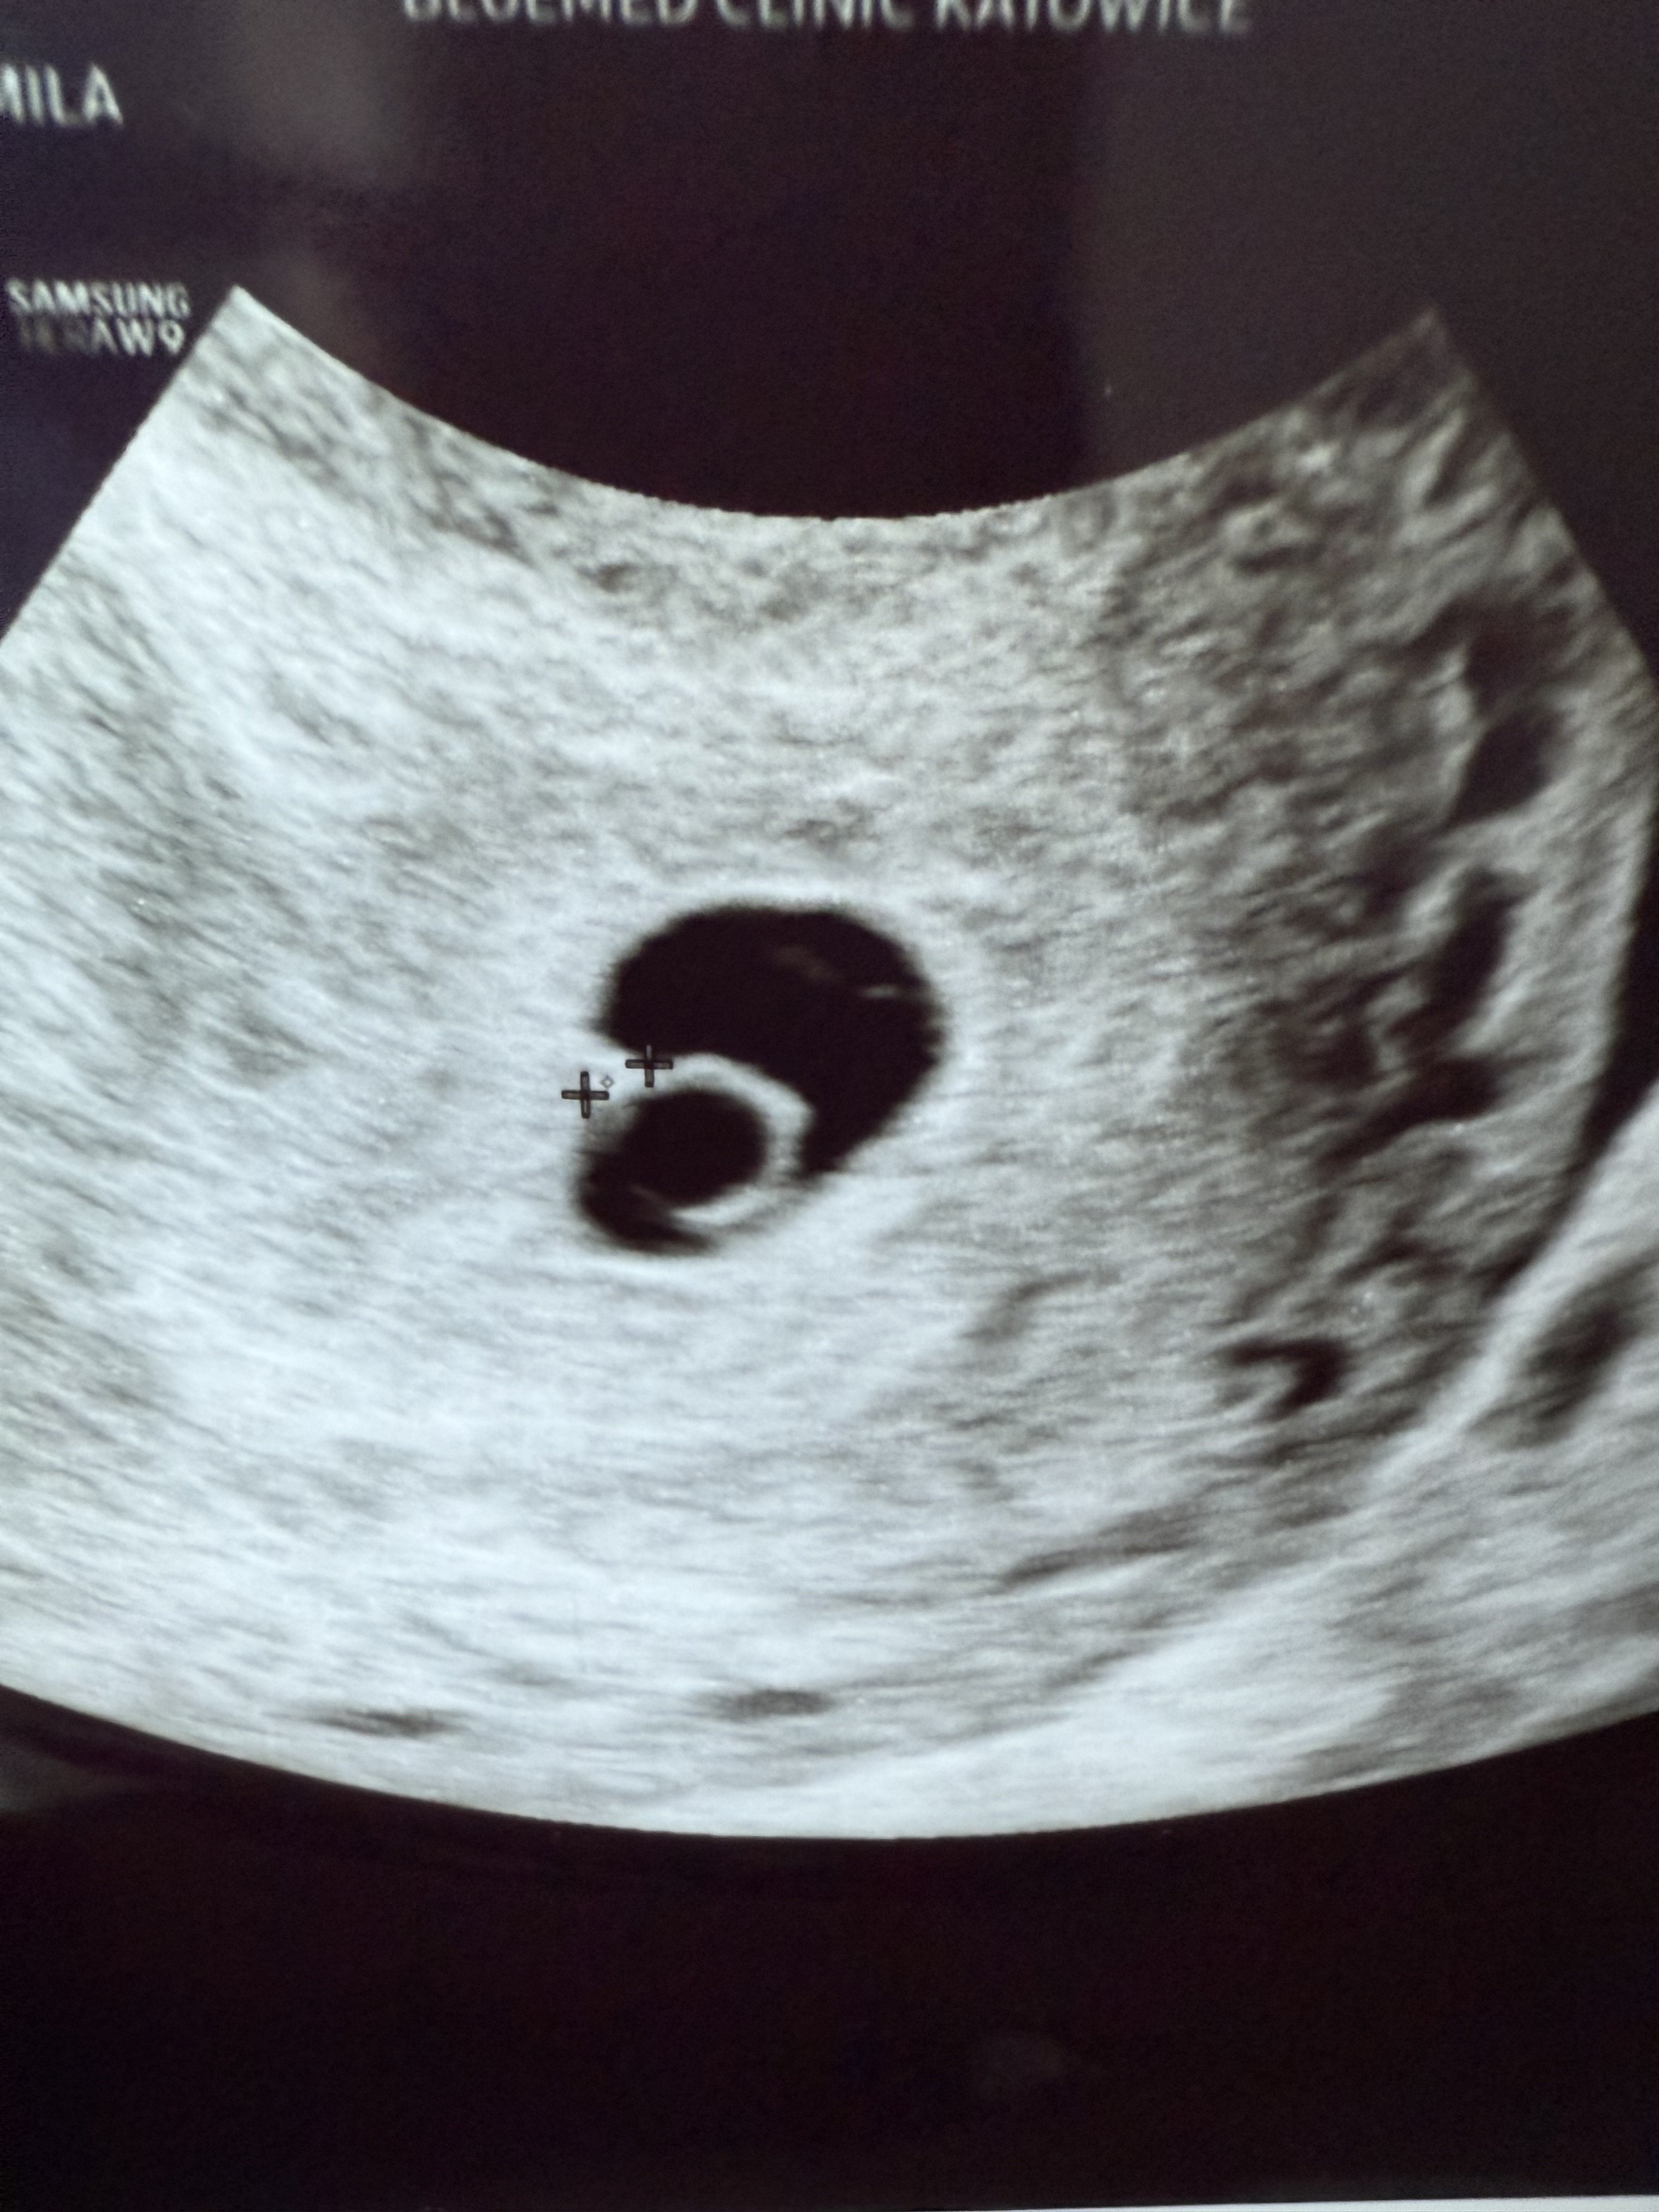

Ja już po, serduszka ani migotania jeszcze nie widać, ale jest ładny pęcherzyk +żółtkowy, a do niego przyklejony Kajtek (przepraszam @loumarie, że zżynam określenie 😆) 1,5mm. 🥹 Mam nadzieję, że Kajtkowi serce bije, tylko za małe żeby zobaczyć. Kontrola za dwa tygodnie, karta ciąży założona. Przepisała mi też Pani Doktor neoparin, także zacznie się jazda 😆

Kropek/Kajtek dziękuje wszystkim kreskowym Ciociom, że tak trzymają za niego kciuki!!! 🥹❤️❤️❤️

• IMG_8645.jpeg